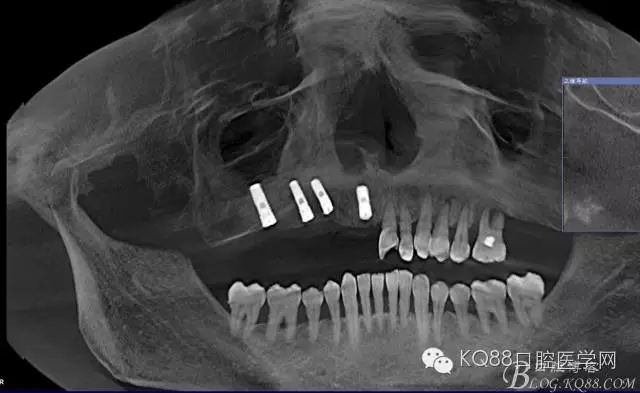

檢查:11、12、13Ⅲ度松動(dòng),牙齦退縮,根面暴露,14、15、16、17缺失,余牙不同程度牙齦退縮。

輔助檢查:ct示骨密度良好,11 12區(qū)域骨下有一水平向埋伏牙,15 16區(qū)域骨高度2.5-3mm,骨寬度6-9mm。

治療計(jì)劃:11 12 13及埋伏牙拔除,同期上頜竇外提升手術(shù)及種植修復(fù)